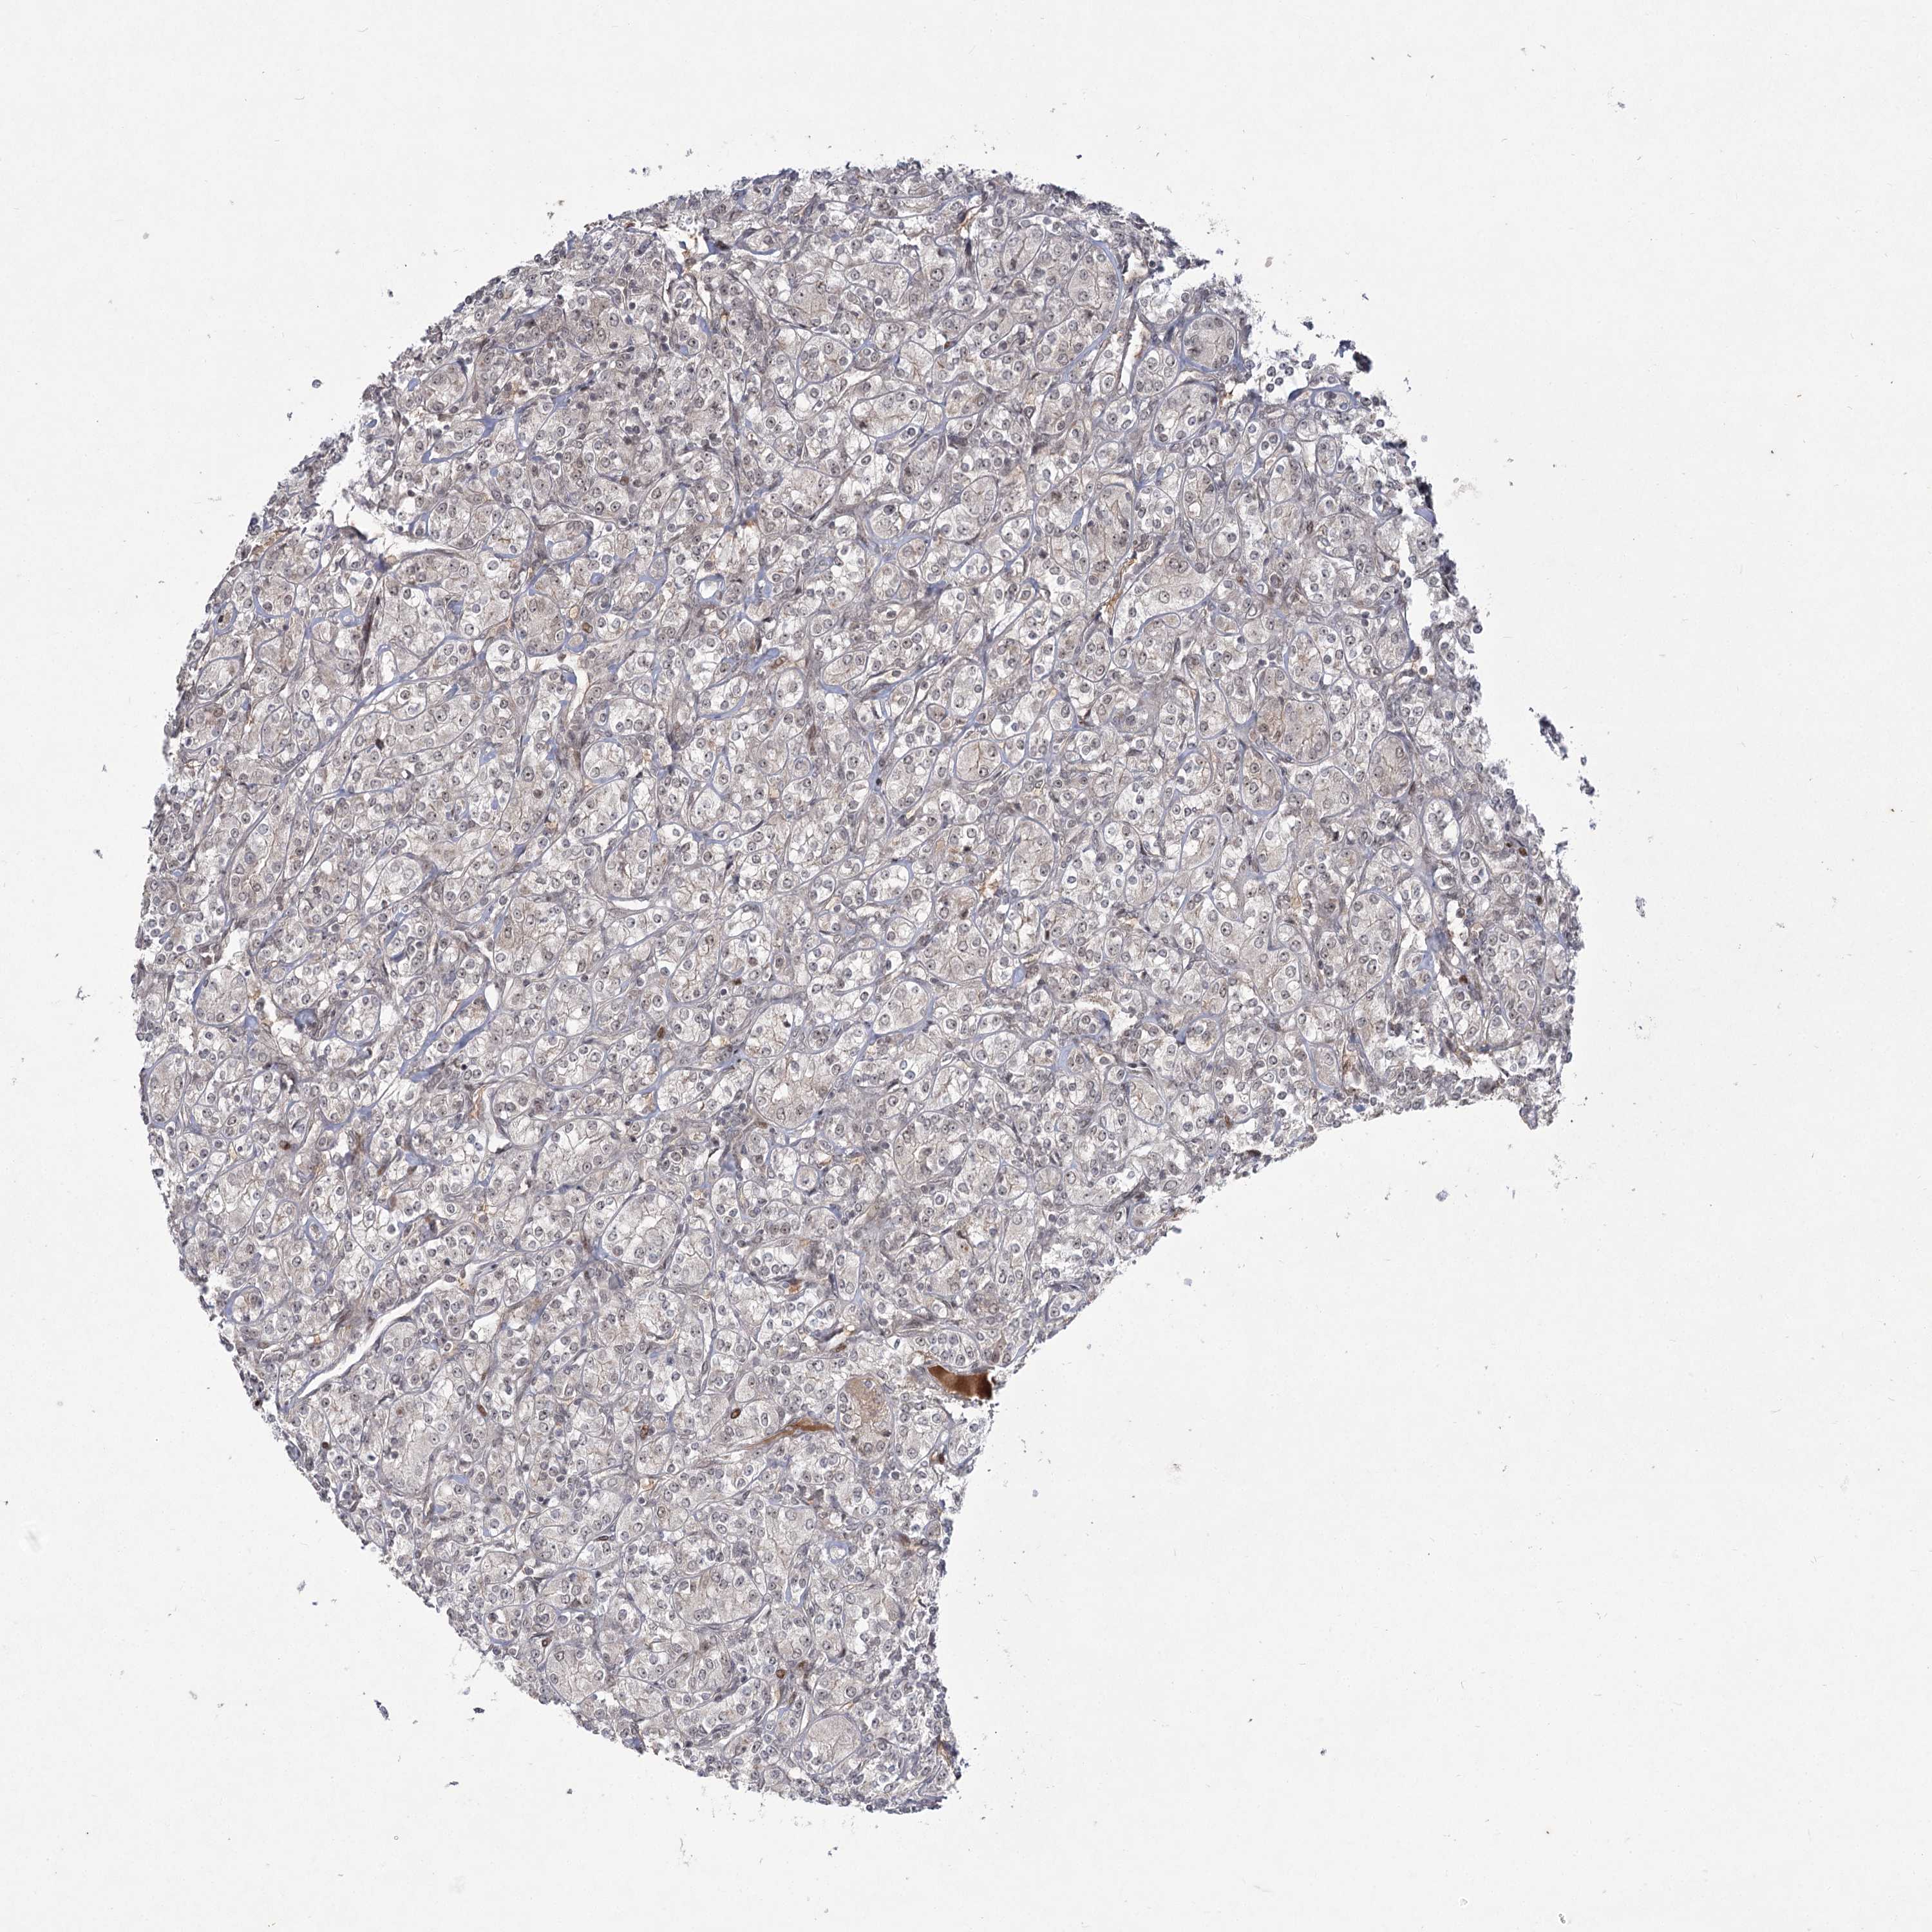

KIDNEY RENAL PAPILLARY CELL CARCINOMA (TCGA) - Interactive survival scatter ploti

The Survival Scatter plot shows the clinical status (i.e. dead or alive) for all individuals in the patient cohort, based on the same data that underlies the corresponding Kaplan-Meier plots. Patients that are alive at last time for follow-up are shown in blue and patients who have died during the study are shown in red.

The x-axis shows the expression levels (FPKM) of the investigated gene in the tumor tissue at the time of diagnosis. The y-axis shows the follow-up time after diagnosis (years). Both axes are complimented with kernel density curves demonstrating the data density over the axes. The top density plot shows the expression levels (FPKM) distribution among dead (red) and alive patients (blue). The right density plot shows the data density of the survived years of dead patients with high and low expression levels respectively, stratified using the cutoff indicated by the vertical dashed line through the Survival Scatter plot. This cutoff is automatically defined based on the FPKM cutoff that minimizes the p-score. The cutoff can be changed by dragging the vertical line or by entering a cutoff value in the square labeled "Current cut-off".

Under the Survival Scatter plot the p-score landscape (black curve; left axis) is shown together with dead median separation (red curve; right axis). Dead median separation is the difference in median mRNA expression between patients who have died with high and low expression, respectively. It is calculated as follows: median FPKM expression of dead patients with high expression - median FPKM expression of dead patients with low expression. This is intended to aid the user in visually exploring custom cutoffs and the associated p-scores and dead median separation.

Individual patient data is displayed and can be filtered by clicking on one or more of the category buttons on the top of the page. Categories describing expression level and patient information include: high, low, alive, dead, female, male and tumor stages. The scale of the x-axis can be toggled between linear and log-scale by clicking on the "x log" button. Mouse-over function shows TCGA ID, patient information and mRNA expression (FPKM) for each patient.

& Survival analysisi

Kaplan-Meier plots summarize results from analysis of correlation between mRNA expression level and patient survival. Patients were divided based on level of expression into one of the two groups "low" (under cut off) or "high" (over cut off). X-axis shows time for survival (years) and y-axis shows the probability of survival, where 1.0 corresponds to 100 percent.

HELQ is not prognostic in Kidney Renal Papillary Cell Carcinoma (TCGA)

Best expression cut offi

: 1.65